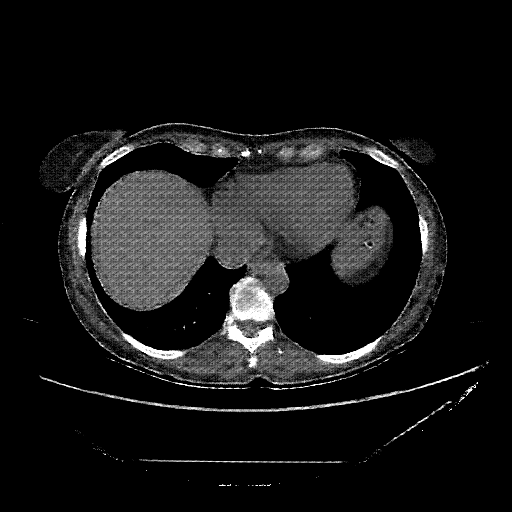

Original VENOUS CT scan

No window - Raw intensity values

Lung window (WL -600, WW 1500 β†’ Low βˆ’1350, High +150)

Mediastinum window (WL 40, WW 400 β†’ Low βˆ’160, High +240)